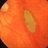

- macular hemorrhage, retina surgery complications, dehemoglobinized hemorrhage

Fundus camera

Topcon VT-50 - Description

- Partially dehemoglobinized macular hemorrhage in a 45-year-old white female following a scleral buckling procedure 4 weeks earlier; the hemorrhage was a complication of external drainage of the SRF; V.A. = 20/200